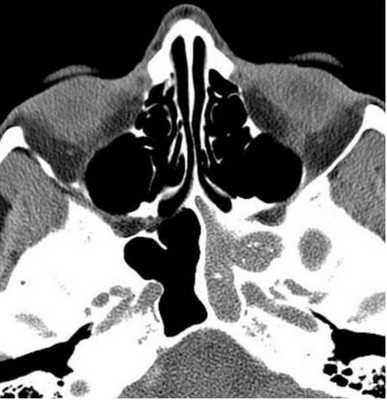

Компьютерная томограмма носовых пазух: правосторонний гайморит